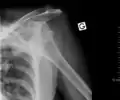

Anterior dislocation of the right shoulder. Y view X ray.